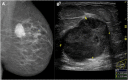

Breast metastases from extramammary cancers are rare and usually related to poor prognosis. The extramammary tumours most frequently exhibiting breast metastases are melanoma, lymphomas, ovarian cancer, lung and neuroendocrine tumours, and sarcomas. Owing to the lack of reliable and specific clinical or radiological signs for the diagnosis of breast metastases, a combination of techniques is needed to differentiate these lesions from primary breast carcinoma or even benign breast lesions. Multiple imaging methods may be used to evaluate these patients, including mammography, ultrasound, MRI, CT and positron emission tomography CT. Clinical and imaging manifestations are varied, depend on the form of dissemination of the disease and may mimic primary benign and malignant breast lesions. Haematologically disseminated metastases often develop as a circumscribed mass, whereas lymphatic dissemination often presents as diffuse breast oedema and skin thickening. Unlike primary carcinomas, breast metastases generally do not have spiculated margins, skin or nipple retraction. Microlobulated or indistinct margins may be present in some cases. Although calcifications are not frequently present in metastatic lesions, they occur more commonly in patients with ovarian cancer. Although rare, secondary malignant neoplasms should be considered in the differential diagnosis of breast lesions, in the appropriate clinical setting. Knowledge of the most common imaging features can help to provide the correct diagnosis and adequate therapeutic planning.